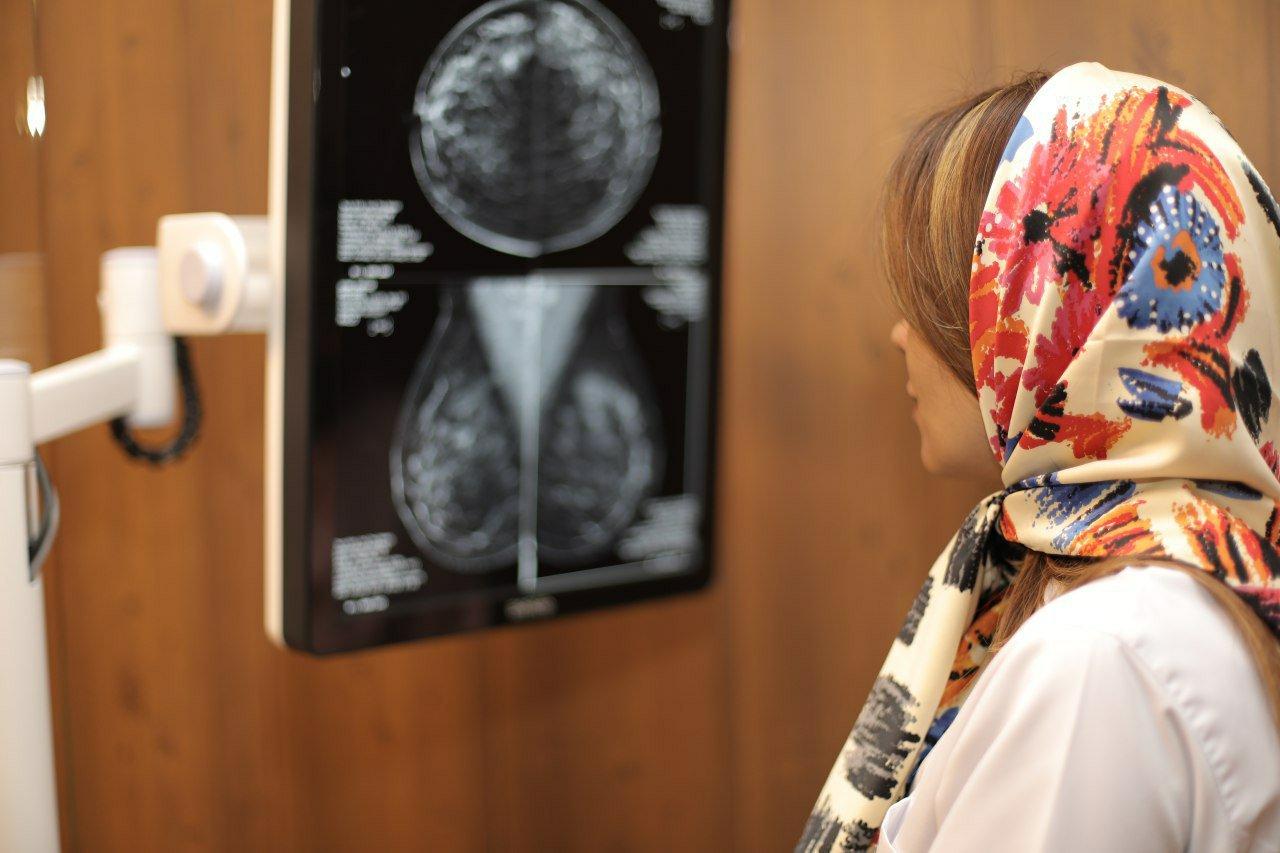

من از خدمات سونوگرافی مرکز تصویربرداری دیجیتال مهر ایرانیان استفاده کردم و بسیار راضی هستم. محیط آرام و بدون استرس و رفتار بسیار مناسب پرسنل جو خوبی رو بوجود آورده بود.